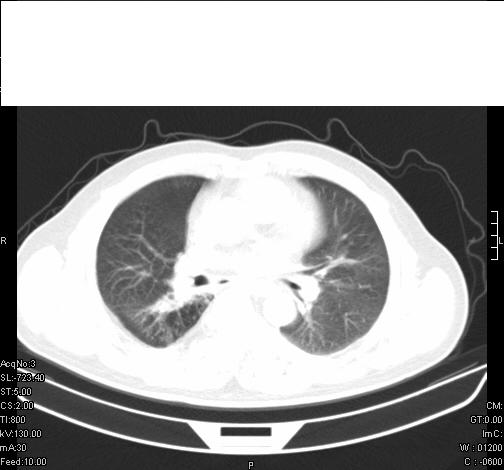

标题: CT6685:右肺阻塞性炎症,增强CT。 [打印本页]

标题: CT6685:右肺阻塞性炎症,增强CT。

前几天,发了患者的平扫片,患者抗炎一周后增强扫描。右中叶病灶吸收明显,但下叶病灶未见明显吸收。右肺门可见结节影,看来凶多吉少

右肺下叶散在的斑片状致密影,下叶支气管变窄。考虑:右肺慢性炎症。

支持:右肺下叶散在的斑片状致密影,下叶支气管变窄。考虑:右肺慢性炎症。

右肺下叶支气管壁不规则增厚,右肺下叶有斑片状影分布。考虑右肺中央型肺癌伴右肺下叶阻塞性改变。建议支纤镜检查。平扫比增强较好显示了病变情况。